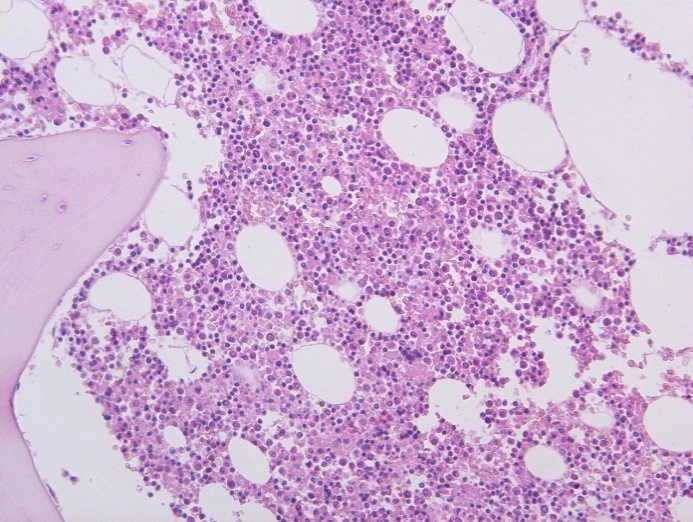

При исследовании ткани легких в стенке сосудов видны плотные гомогенные массы, дающие положительную реакцию на амилоид. При исследовании органов в поляризационном микроскопе обнаружено зеленоватое свечение амилоида. В костном мозге скопление клеток, дающих положительную реакцию с моноклональными антителами к CD38 (рис. 5, 6).

Рис. 5. Пролиферация клеток костного мозга. Окраска гематоксилин-эозин, ×200

Патологоанатомический диагноз: Первичный амилоидоз c поражением почек, селезенки, миокарда, легких. Уремия. Водянка серозных полостей.

Таким образом, у больного был амилоидоз с поражением почек, селезенки, сердца и легких. Обнаружение в костном мозге пролиферации лимфоцитов, дающих реакцию с моноклональными антителами к CD38, дает основание предполагать развитие первичного амилоидоза, который связан с гиперпродукцией легких цепей иммуноглобулина с последующим образованием в тканях внутренних органов AL-амилоида.